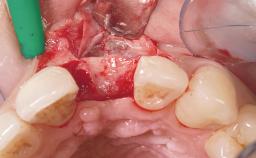

Immediate Flapless Placement of an Implant in a Maxillary Left Central Incisor Site

A 42-year-old female patient was referred to our clinic at the School of Dentistry of the University of São Paulo in November 2004, presenting a deficient restoration in the upper left central incisor. The clinical examination revealed no gingival retraction or any signs of gingival inflammation and, therefore, previous periodontal treatment was not considered. The patient presented a high lip line at full smile and a thin tissue biotype. This combination characterized a high-risk situation from an anatomic point of view, which required careful preoperative planning and cautious surgical execution.

Placement Protocol Immediate implant placement

Tooth Site Maxillary incisor or canine

Socket Morphology Single-root socket

Socket Integrity Sufficient, with intact bone walls

Bone Volume Sufficient, with intact walls